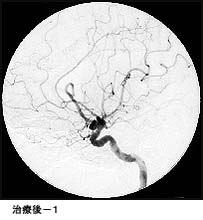

脳動静脈奇形に対する液体塞栓物質を用いた治療

治療により異常血管は閉塞されました。